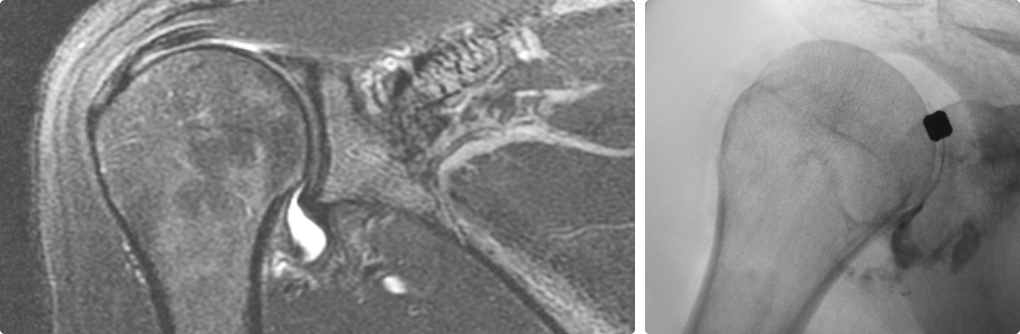

오십견은 어깨를 감싸고 있는 관절 조직인 관절낭에 염증이 발생하면서

유착되어 어깨의 움직임이 제한되고 통증이 유발되는 질환입니다.

오십견은 얼어버린 어깨라고들 부릅니다. 어깨가 움직이는 범위가 점점 줄어들면서

통증을 느끼는 질환입니다. 의학적인 용어로는 동결견, 유착성 관절낭염이라고도 합니다.

즉각적으로 통증을 완화해주고 어깨의 가동범위를 개선해주는 시술입니다.